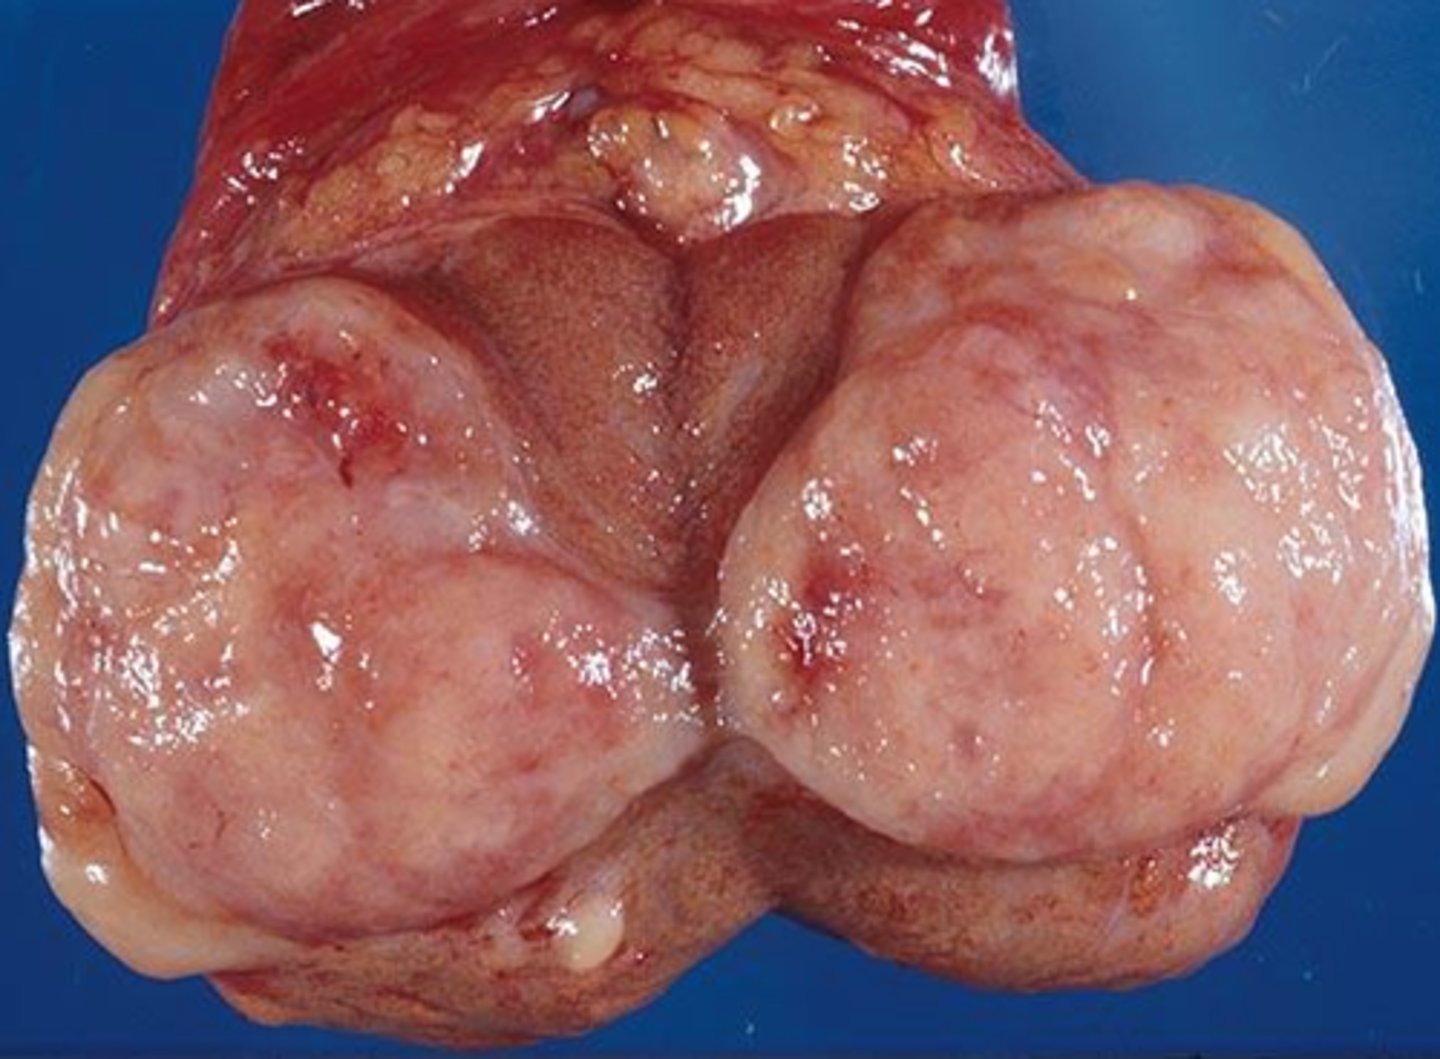

What type of germ cell tumor is characterized by a soft and large mass which remains localized, is painless, is sometimes associated with high hCG, is radiosensitive, has late lymphatic mets, and can often be cured ?

seminoma

seminoma cells

large and uniform with round nuclei